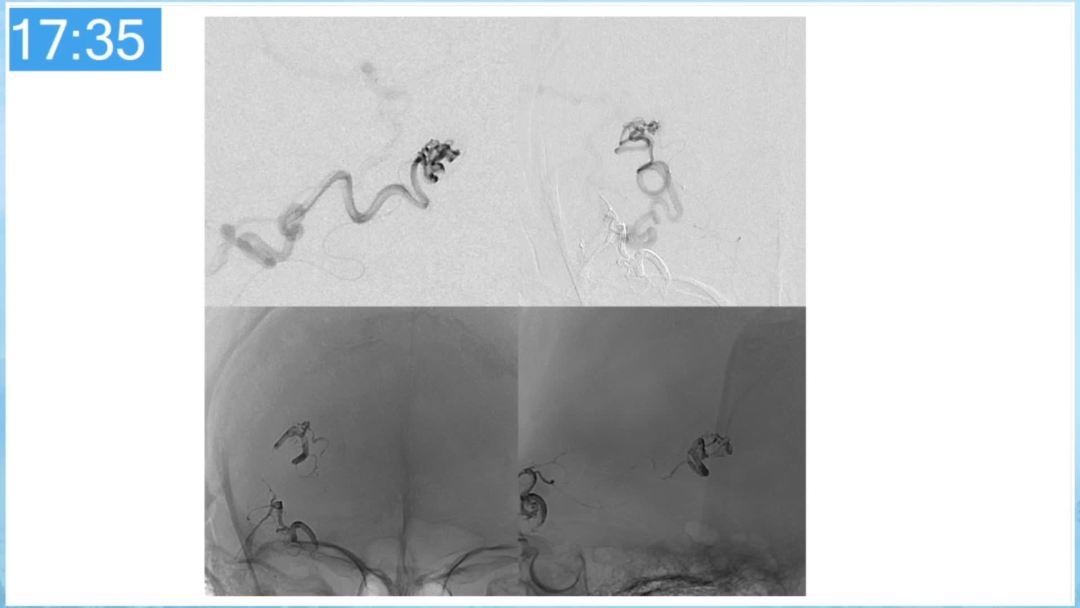

合理的复合平台下的综合治疗,针对每一个病变对应不同方法安全性分析,不预设、不排斥,每种技术发挥到最佳,互相保障。

本期为大家特别分享:空军军医大学唐都医院邓剑平教授的精彩会议内容《颅内动静脉畸形的复合手术治疗》,欢迎大家阅读和分享!